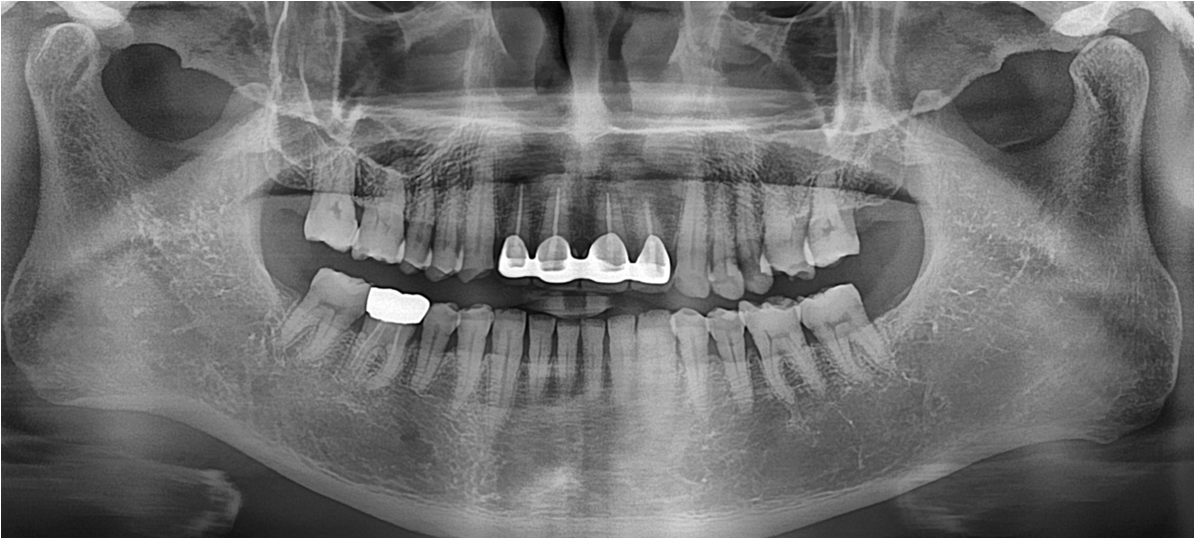

신경치료 후 심미보철

앞니 벌어짐은 라미네이트 치료를 고려할 수 있는데

해당 환자분의 경우 상악, 하악 전치부 교합이 강해 마모가 심한 상태고

시린증상도 있어서 신경치료를 진행하여 시린 증상을 유발하는 원인을 제거하고

크라운 보철치료를 하는 것으로 선택하였습니다.